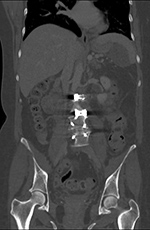

| Zero-Profile lumbar fixation L2-L5 |

| 45 year-old woman with L2-5 anterior lumbar interbody fusion (ALIF) for low back pain. The lateral views are respectively in neutral and flexion positions. The CT images are selected slices in the coronal and sagittal planes, respectively. |

| 45 year-old woman with L2-5 anterior lumbar interbody fusion (ALIF) for low back pain. |